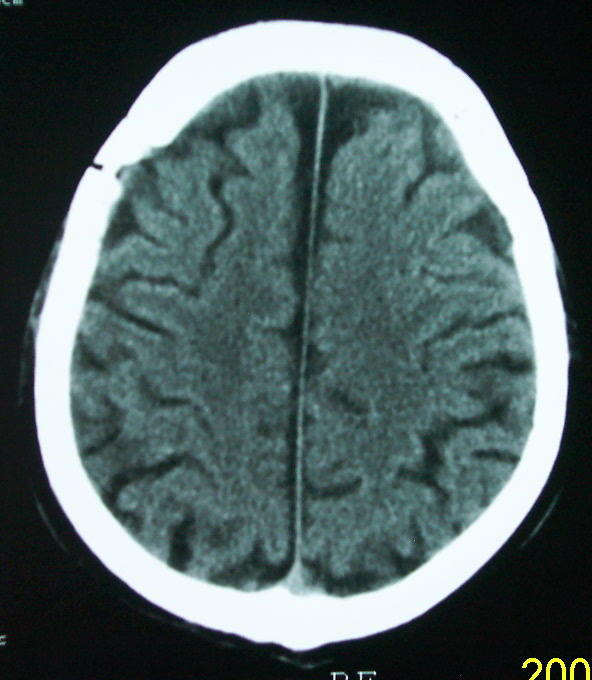

以下是引用余辉在2009-4-15 20:49:00的发言:[br]右侧病灶发生于冠状缝区,但额骨左侧鳞也有病灶,病灶区脑沟裂增宽(有脑萎缩征像,把这个征像放在颅骨病变一起考虑可能有点牵强),是否可能是板障血管畸形所致谢?抑或是嗜酸性肉芽肿或蛛网膜粒压迹那类东西?

以下是引用whzht在2009-4-15 20:57:00的发言:[br]1、额骨改变,考虑蛛网膜粒压迹;[br]2、脑萎缩。